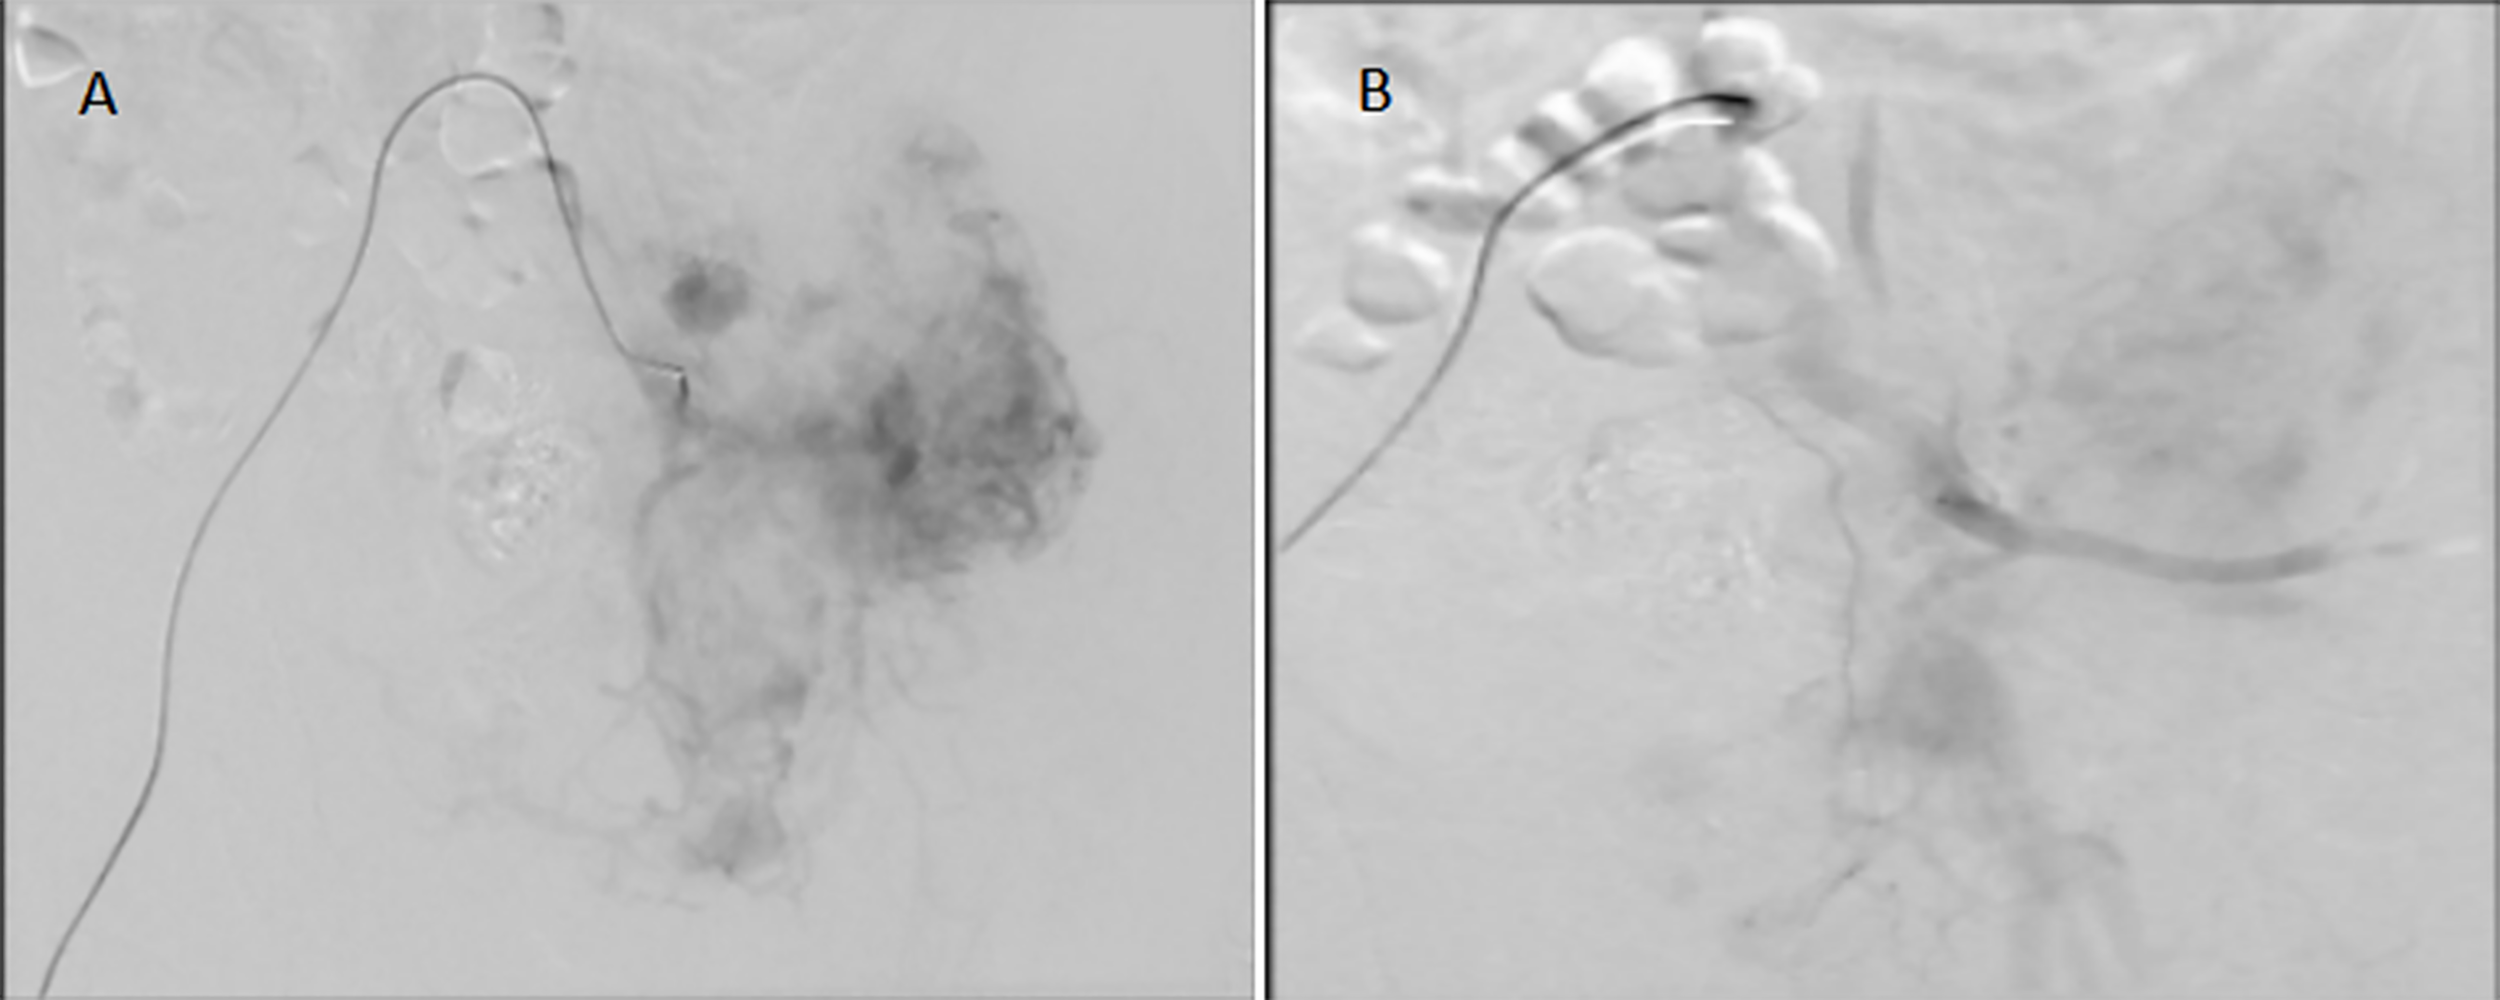

Figure 5

Embolization of the left pelvic tumor artery. (A): before tumor artery embolization; (B):after tumor artery embolization.